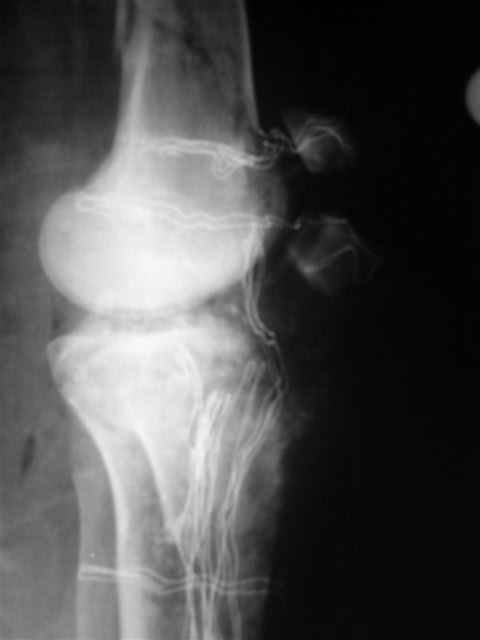

Отправитель: Evgueny Tschekashkin 19 Декабрь 2004, 23:02

Я предупреждал, что ничего сверхъестественного. Каюсь, что одна из спиц прошла несколько дальше, чем нужно было, но главное - перелом стабилизирован и больной работает суставом в полном объёме, несмотря на представленную раннее травму коленного сустава.

Евгений И Чекашкин